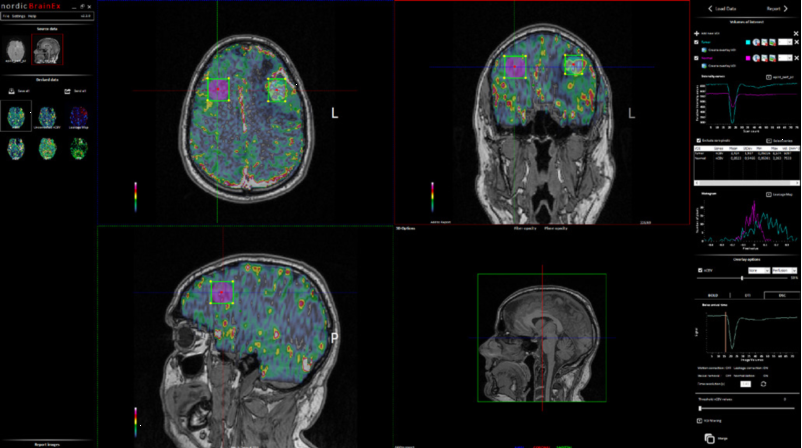

NordicBrainEx是專爲臨床設計的fMRI後處理軟件。簡易而功能強大的界面提高瞭(le)用戶的工作效率。先進的感興趣體積工具、BOLD激活區域的2D/3D可視化、DTI纖維追蹤成像和灌注MRI圖讓臨床醫生可對病竈周圍區域的大腦組織進行廣泛且深入的評估。(對於(yú)腫瘤的分類,分級,術中導航以及治療後的跟蹤監測有重要作用)

4.高效計(jì)算灌注圖(CBV、未校正的CBV、CBF、MTT和血管圖),包含自動(dòng)标準化、滲漏校正和血管移除算法。

5.創(chuàng)建感興趣體積提取量化參(cān)數值,信号強度曲線和直方圖。

Perfusion 模塊